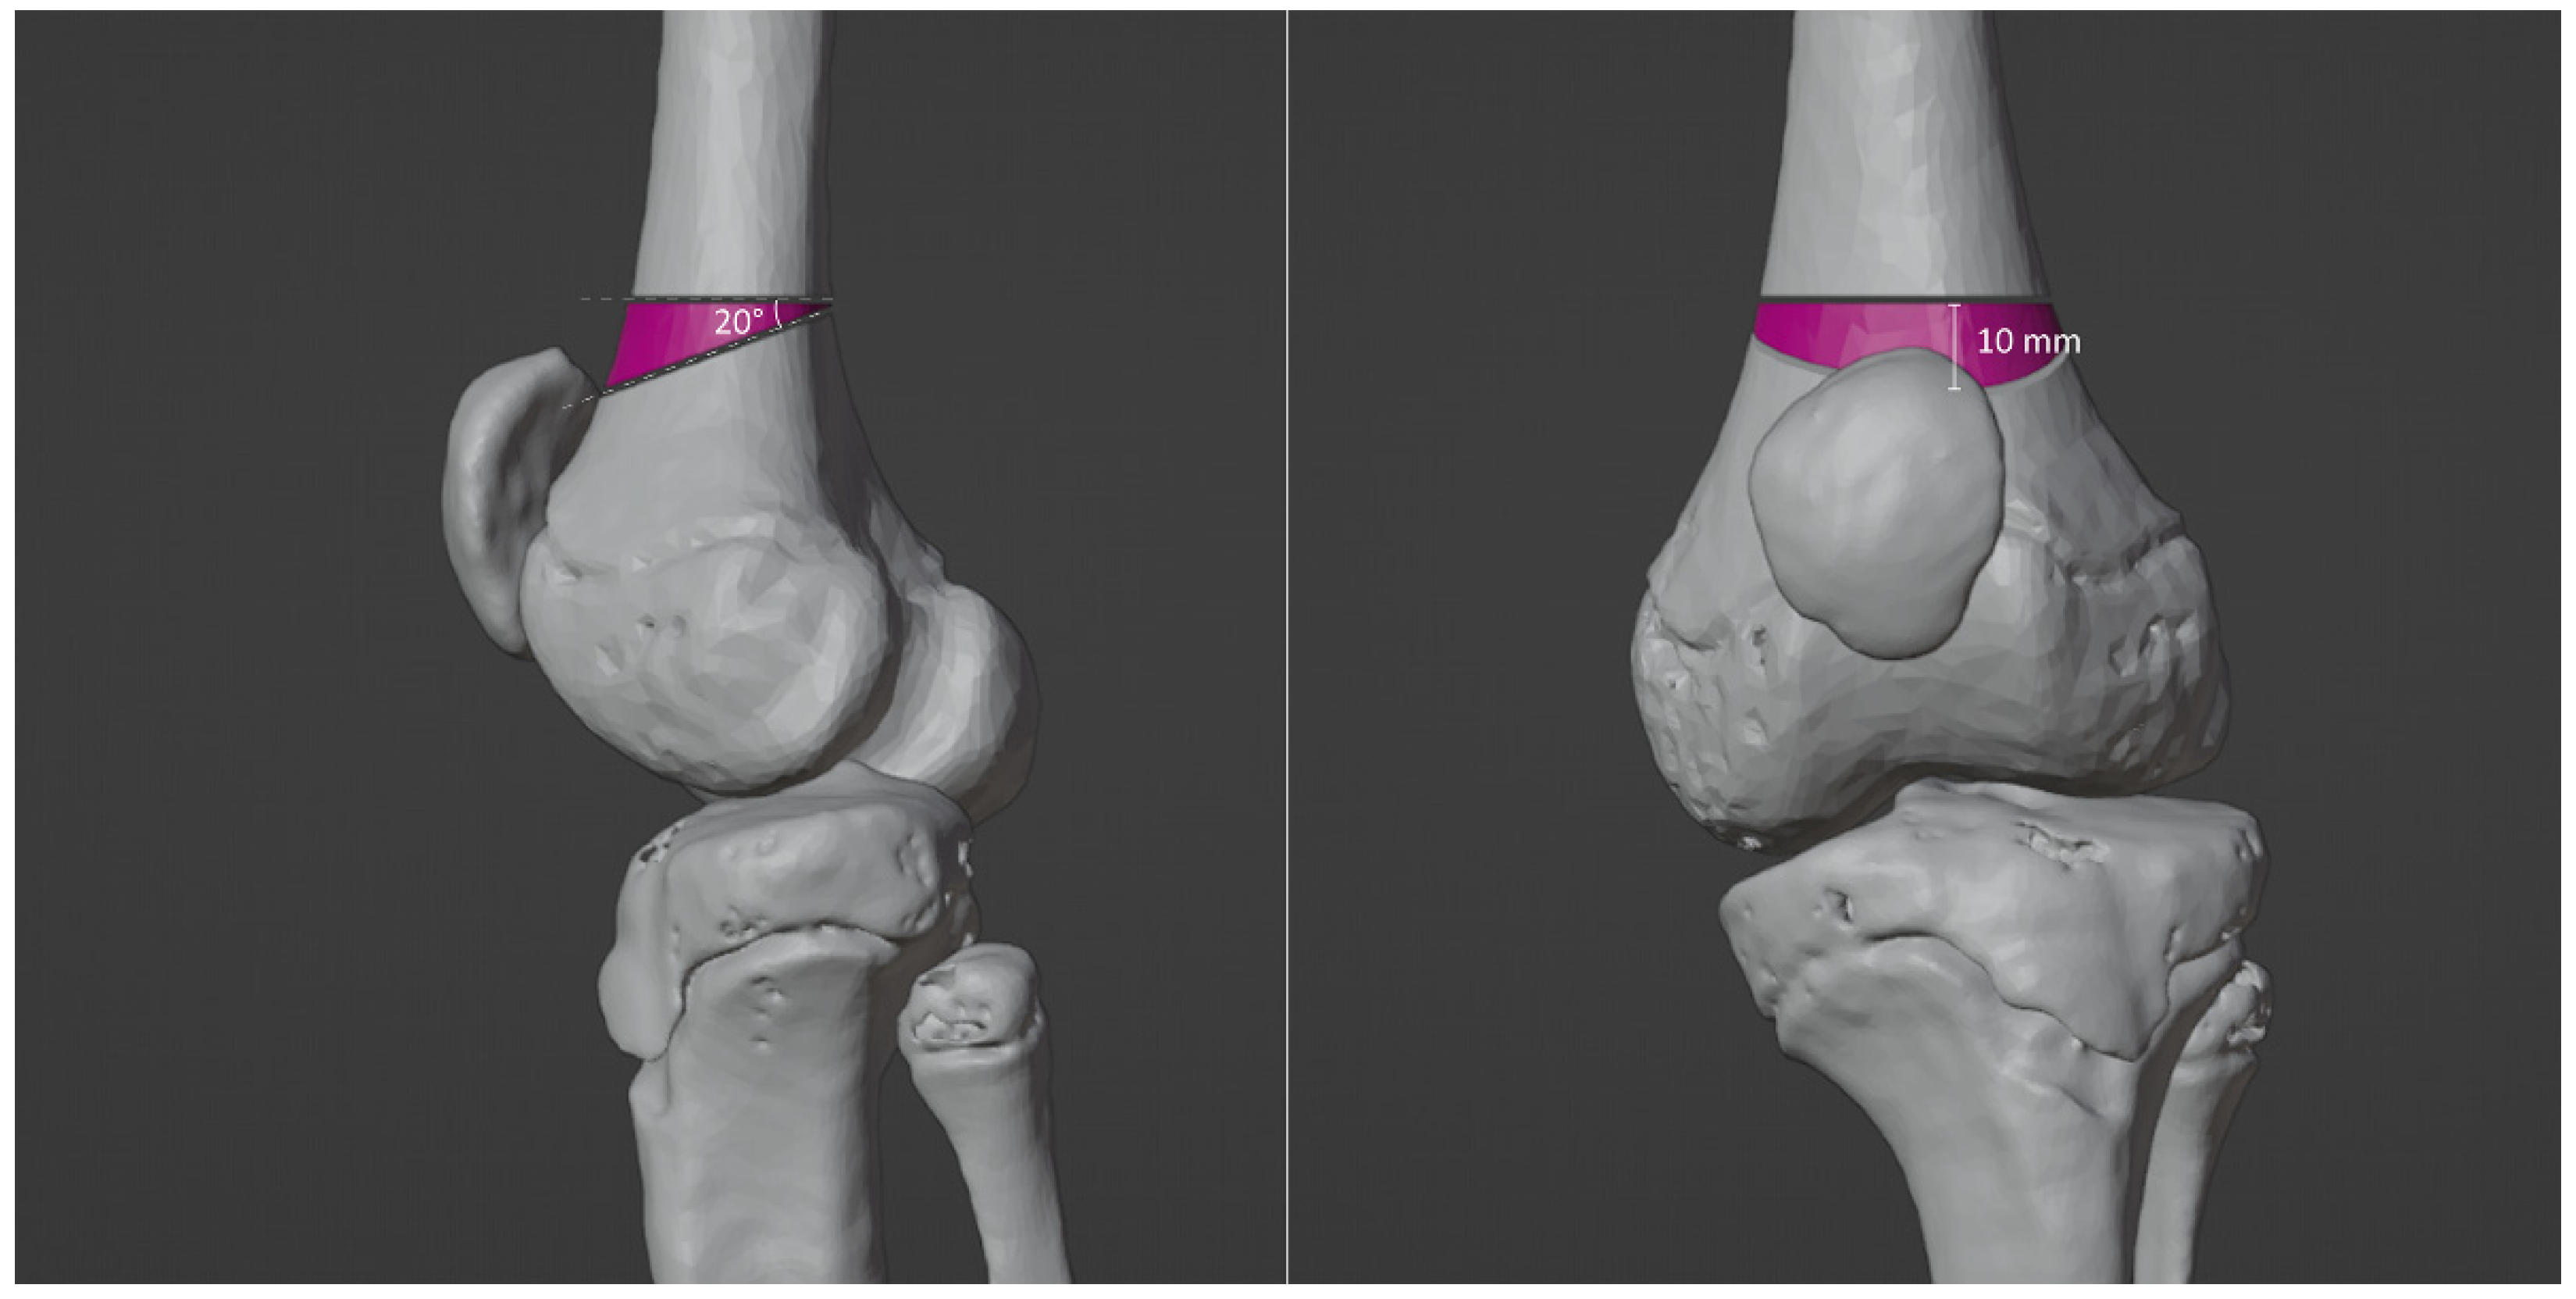

3.4. Virtual Surgical Simulation